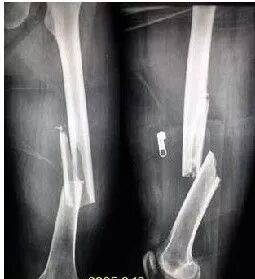

4. 胫腓骨骨折术后功能锻炼

(1)外固定后早期,疼痛减轻即刻进行股四头肌静止收缩运动,髌骨被动活动及足部跖趾关节和趾间关节活动。(见图 17、图 18)

(2)外固定去除后,伤口愈合,可充分练习下肢各个关节活动,并逐步去拐行走。(见图 23)

(3)增加髋、膝、踝关节活动练习,可做起立与坐下练习,健肢站立,患肢做髋屈伸、内收。外展活动,膝、踝关节去说活动,踝关节内外翻抗阻活动。(见图 24)

注意:功能锻炼时要坚持锻炼,活动幅度和力量要循序渐进。外固定早期禁止在膝关节伸直的情况下旋转大腿,以免影响骨折稳定。